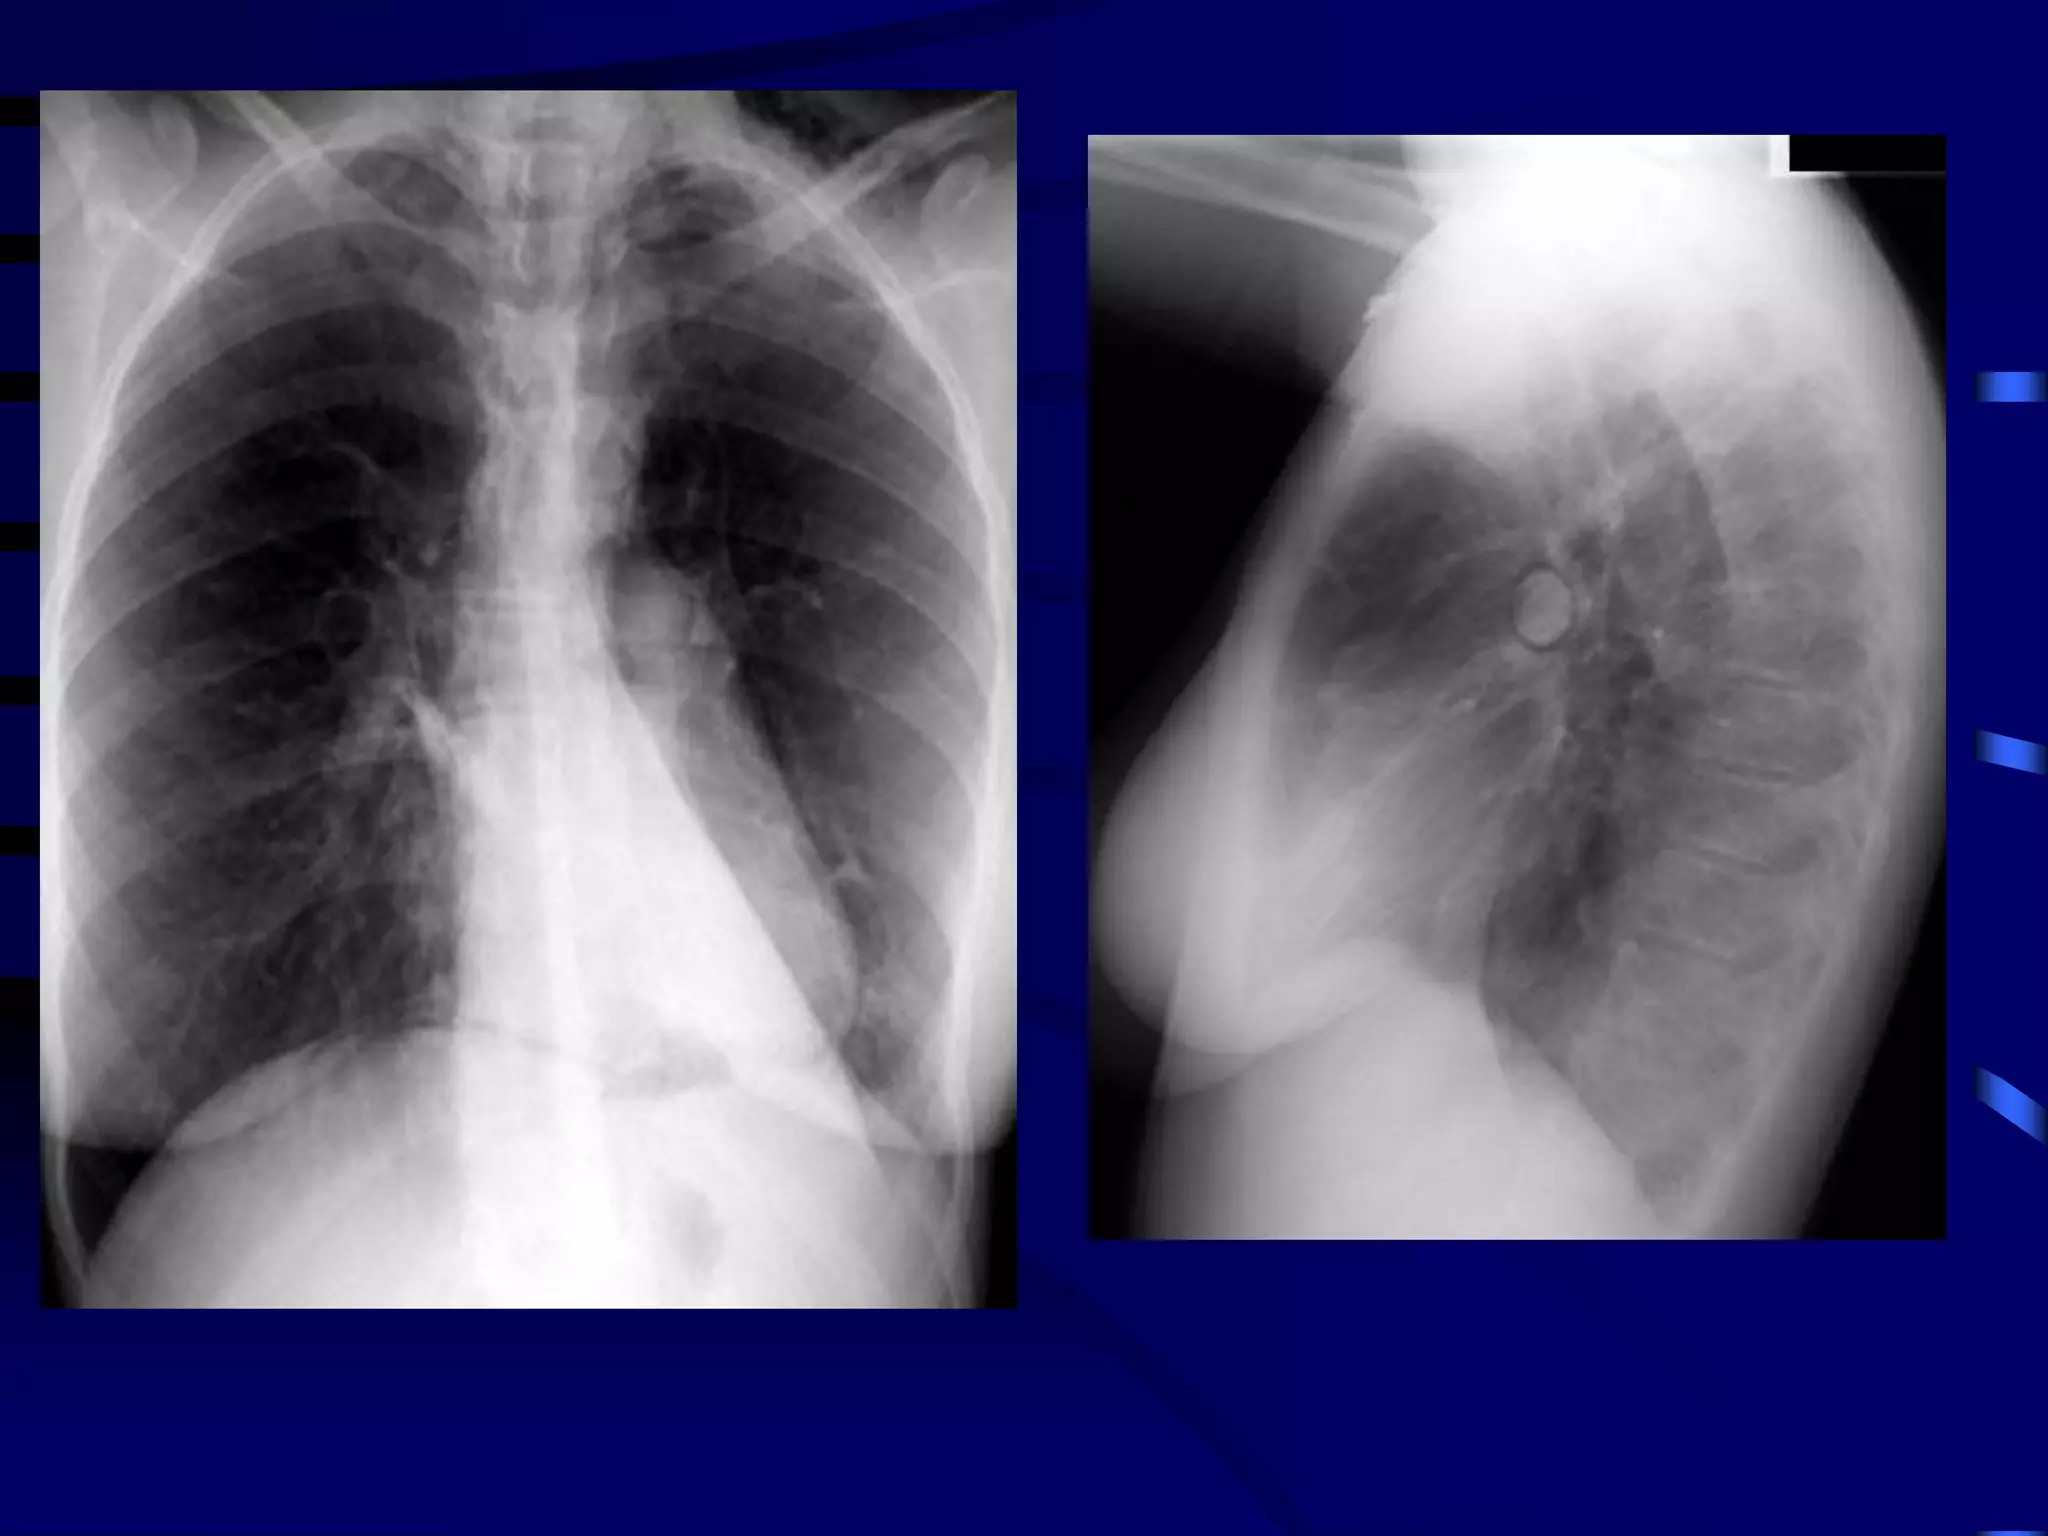

Bronchiolitis

136

What Is Bronchiolitis?

 Bronchiolitis is acute inflammation

of the airways, characterised by

wheeze

 Bronchiolitis can result from a viral

infection

 Respiratory Syncytial Virus (RSV)

may be responsible for up to 90%

of bronchiolitis cases in young

children

Hall CB, McCarthy CA. In: Principles and Practice of Infectious Diseases 2000:1782-1801;

Panitch HB et al. Clin Chest Med 1993;14:715-731